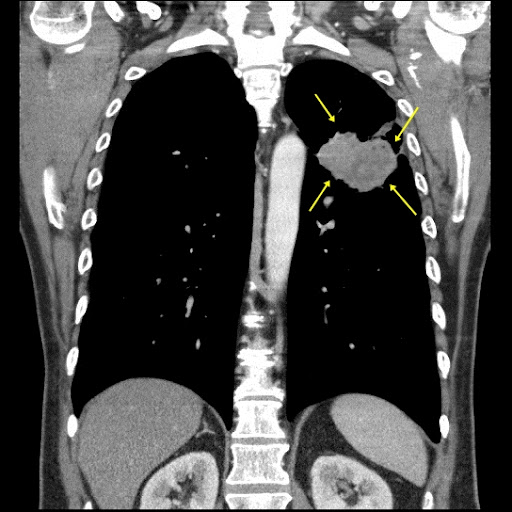

간은 인체에서 가장 큰 장기 중 하나로, 여러 가지 중요한 기능을 수행합니다. 간 질환은 매우 일반적인 문제로, 신속하고 정확한 진단이 필요합니다. 복부 CT를 통해 간의 경화, 종양, 지방간 등 다양한 문제를 확인할 수 있습니다. 특히 간암의 경우, CT 촬영은 초기 단계에서 종양의 크기와 위치를 평가하는 데 중요한 역할을 합니다. CT 이미지는 간 내 혈관과 주변 조직의 상태를 상세히 보여주기 때문에, 간암이 다른 장기로 전이되었는지 파악하는 데도 유용합니다.

간암은 조기 증상이 거의 없기 때문에 진단이 늦어지는 경우가 많습니다. 그러나 복부 CT를 통해 초기 증상을 발견할 수 있다면, 치료 옵션이 훨씬 다양해집니다. 간암의 원인으로는 간염 바이러스 감염, 알코올 남용, 비만 등이 있으며, 이들 요인을 관리함으로써 예방할 수 있습니다. CT 촬영을 통해 조기에 간암을 발견하면, 간 절제술이나 간 이식과 같은 치료를 통해 생존율을 높일 수 있습니다.